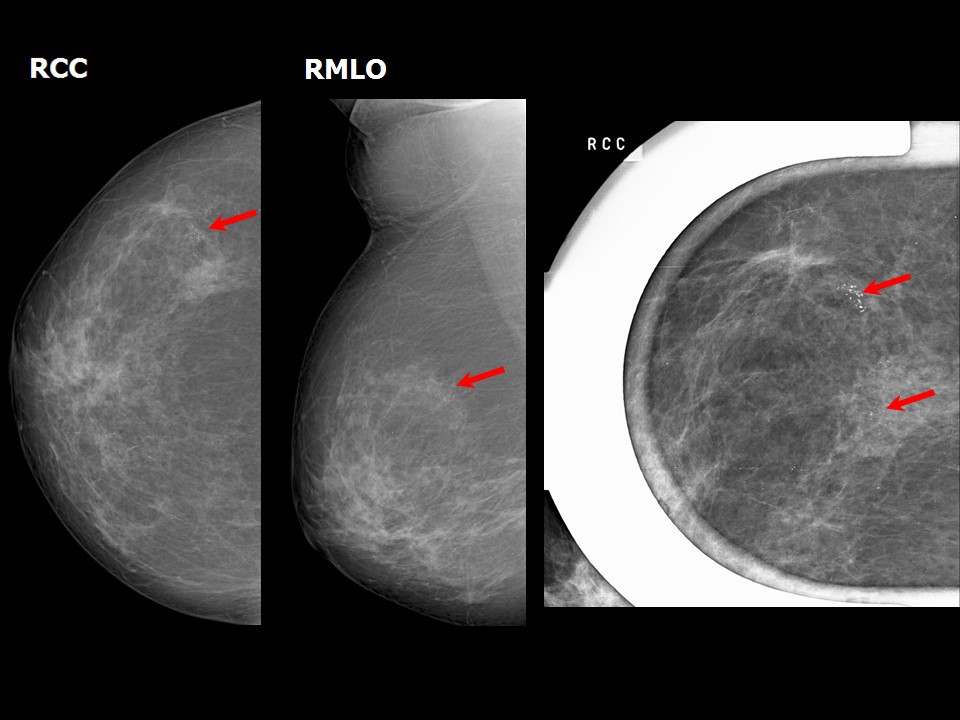

From screening.iarc.fr

Atlas of breast cancer early detection What Do Calcium Deposits In Breast Mean Breast calcifications are small pieces of calcium deposited into breast tissue and are very common. They are very common and are usually benign (noncancerous). In some instances, certain types of. Often not cancerous, breast calcifications are detected on mammograms. They appear as white spots or flecks on a mammogram. Breast calcifications are calcium deposits within breast tissue. As breast cells. What Do Calcium Deposits In Breast Mean.

Atlas of breast cancer early detection What Do Calcium Deposits In Breast Mean Called calcifications, these deposits can appear as bright white specks in mammograms. They’re common and often show up on a routine. Breast calcifications are calcium deposits within breast tissue. Often not cancerous, breast calcifications are detected on mammograms. As breast cells grow and divide, calcium deposits can build up in breast tissue. In some instances, certain types of. Breast calcifications. What Do Calcium Deposits In Breast Mean.